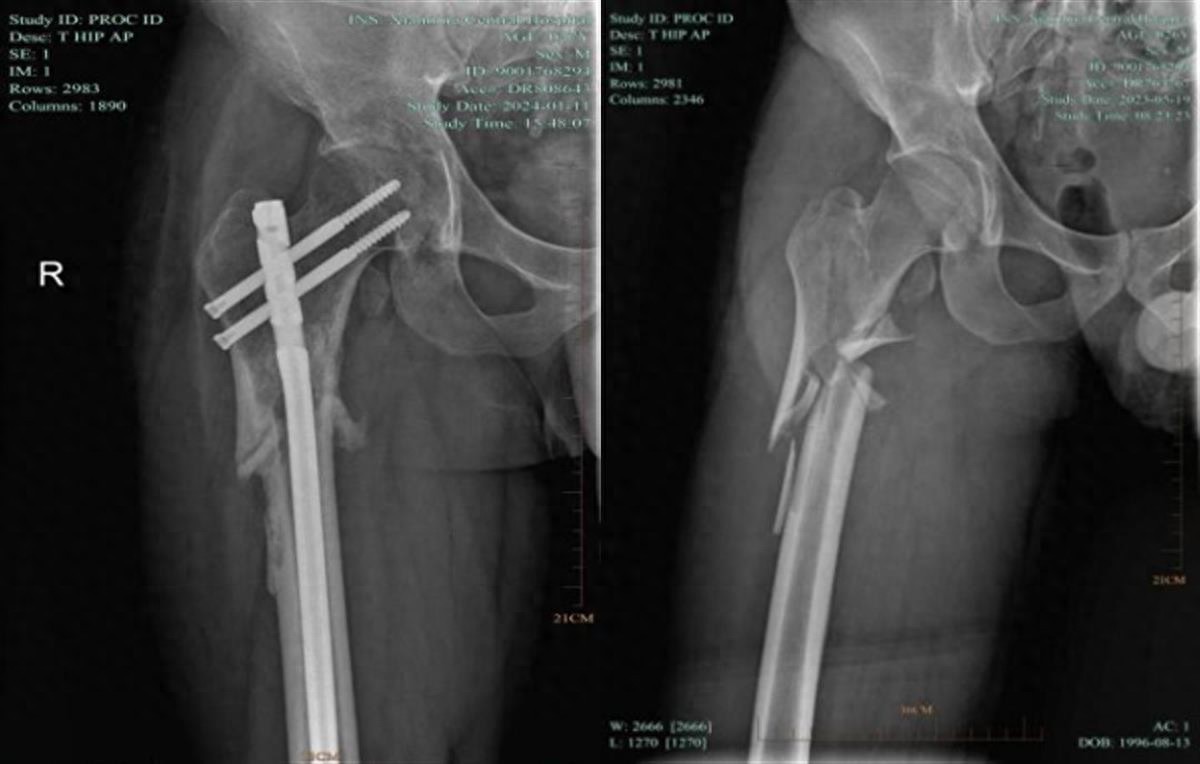

2023年5月,26岁的裴先生因公出差至咸宁,不幸遭遇车祸,导致右髋关节严重受伤,诊断为“右侧股骨上段粉碎性骨折”。突如其来的伤痛让他陷入身心双重困境:疼痛难忍、活动受限,甚至出现心慌、失眠和食欲不振。在异地他乡的无助时刻,关节外科、运动医学科医护团队给予了裴先生无微不至的关怀,从专业角度反复分析病情,给予他关心和安慰,每日查房时都会鼓励他坚持康复锻炼,用温暖的话语激发他的斗志。

面对复杂的病情,科室医护团队迅速制定个性化手术方案,并同步开展心理疏导。“医生不仅分析病情,还像家人一样鼓励我。”裴先生回忆道。2023年6月2日,团队为其成功实施“右侧股骨上端粉碎性骨折闭合复位内固定术”。术后,医护人员每日跟进康复进展,用专业指导和暖心话语助他重燃信心。

术前术后对比图

今年初,裴先生需取出内固定物时,他毫不犹豫再次跨越三千公里返咸。“在这里,我感受到家的温暖,只有他们能让我放心。”这份信任,最终化为第二面锦旗上的赞语:“医德高尚医术精,关爱病患暖人心”。